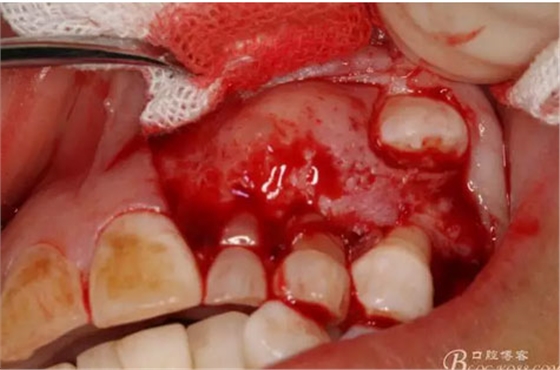

圖12.用小骨鑿去除覆蓋在牙瘤表面的骨質(zhì)。發(fā)現(xiàn)牙瘤的包膜。

圖13.暴露出部分牙瘤

圖14.沿一側(cè)骨壁逐步剝離牙瘤組織。